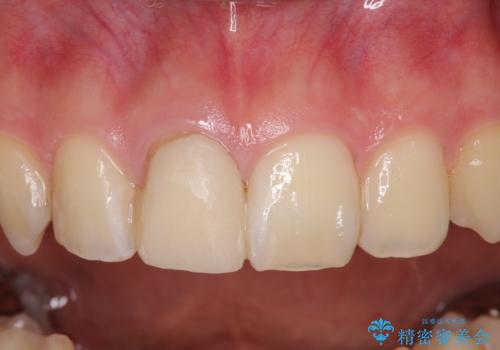

- 治療中の前歯と口腔内にある銀歯が気になるとのことで来院された患者様です。

口腔内の金属が全てなくなり、患者様には大変満足していただきました。